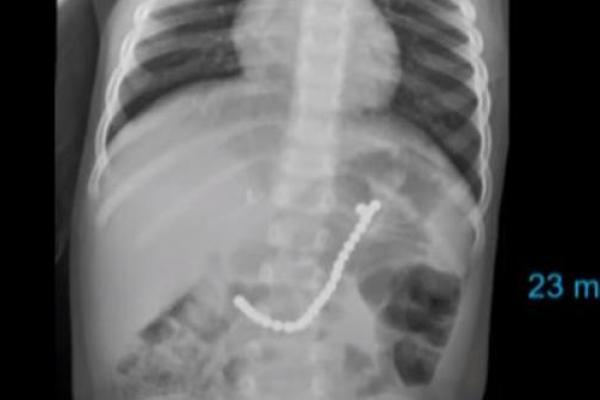

Nahas, Balita Ini Harus Dioperasi Usai Telan Puluhan Manik-manik Gambar perut balita yang menelan 23 manik-manik (foto: UPI)

Jakarta, Katakini.com - Balita asal Tennessee akhirnya menjalani operasi ketika X-ray mengungkapkan ia telah menelan 23 manik-manik magnetis.

Nikki Cooke mengatakan putranya, Caiden, 2, sedang mengunjungi dokter anak ketika hasil rontgen mengungkapkan bocah itu menelan 23 manik-manik magnetis.